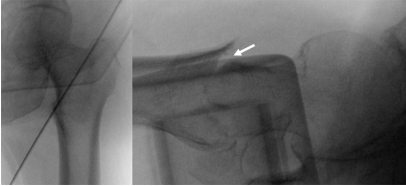

这种特定骨折类型在闭合复位时,前后位片上很容易实现准确复位,但在侧位片上存在持续的前方皮质不连续,必须通过手法将其复位到位置(图2)。

图 2. 在骨折床上闭合复位后,前后位片上复位良好(移位在1个皮质厚度以内)(左图),但在骨折床上闭合复位后,侧位片上存在前侧皮质不连续(移位超过2个皮质厚度)(右图)。

然后将骨钩尖端钩住近端骨块,通过围绕骨钩纵轴旋转、抬起塌陷的近端骨块,最终解除其嵌插来进行复位(图4)。

图 4. 在实际病例和模拟中,通过转动骨钩将近端骨块从远端骨块中撬出。前侧皮质得到复位(箭头所示)。